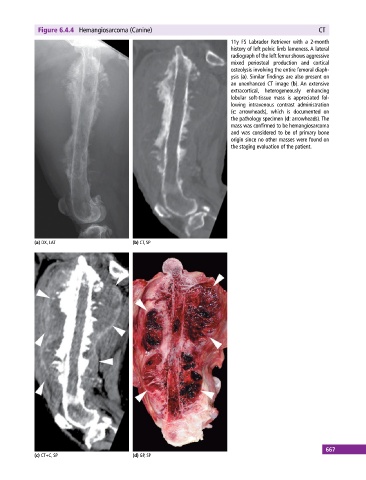

Figure 6.4.4 Hemangiosarcoma (Canine) CT

11y FS Labrador Retriever with a 2‐month

history of left pelvic limb lameness. A lateral

radiograph of the left femur shows aggressive

mixed periosteal production and cortical

osteolysis involving the entire femoral diaph-

ysis (a). Similar findings are also present on

an unenhanced CT image (b). An extensive

extracortical, heterogeneously enhancing

lobular soft‐tissue mass is appreciated fol-

lowing intravenous contrast administration

(c: arrowheads), which is documented on

the pathology specimen (d: arrowheads). The

mass was confirmed to be hemangiosarcoma

and was considered to be of primary bone

origin since no other masses were found on

the staging evaluation of the patient.

(a) DX, LAT (b) CT, SP

(c) CT+C, SP (d) GP, SP